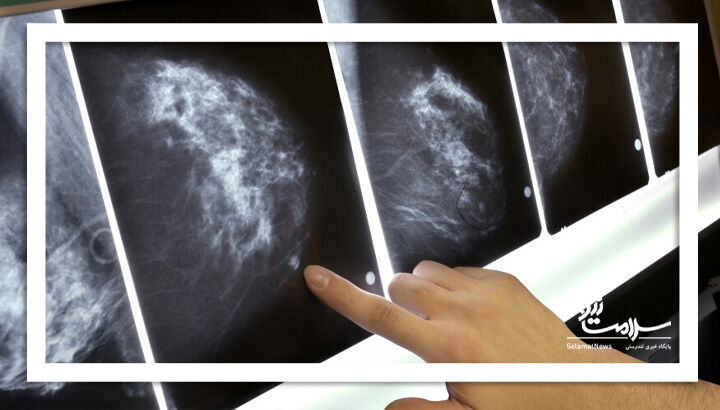

وی گفت: انجام منظم ماموگرافی، نقش کلیدی در تشخیص زودهنگام سرطان پستان دارد. همچنین با غربالگری به موقع می توان میزان بقای مبتلایان را به طور چشمگیر افزایش داد.

وی به برنامه های غربالگری سرطان پستان اشاره کرد وافزود: در سال گذشته، ۱۰۵هزار و ۸۲۲ مورد از زنان بین سنین ۳۰تا ۶۹ سال غربالگری انجام گرفته که از این تعداد ۳هزار و۱۷۹ نفر مشکوک و ۶۰ نفر بدخیم و پیش بدخیم تشخیص داده شده که به مراکز درمانی جهت مداوا معرفی شدند.

شریفی اضافه کرد: همچنین در ۹ ماهه اول امسال ۸۸هزار و ۳۸۸مورد از زنان نیز غربالگری سرطان پستان انجام شده که ازاین تعداد ۲۸نفر بدخیم و پیش بدخیمی شدند.